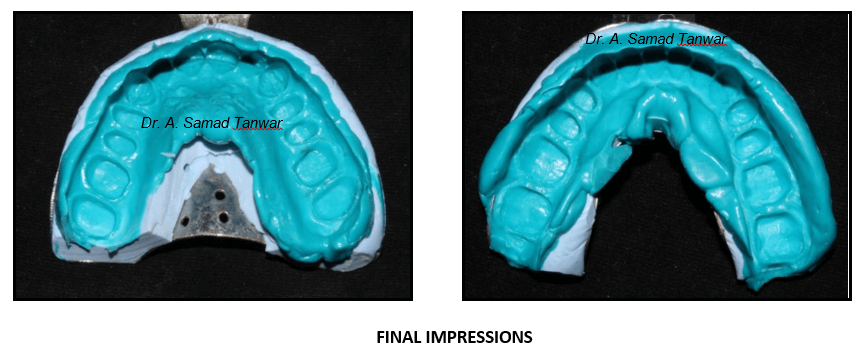

Double mix double step impressions were made using PVS elastomeric impression material

Double mix double step impressions were made using PVS elastomeric impression material